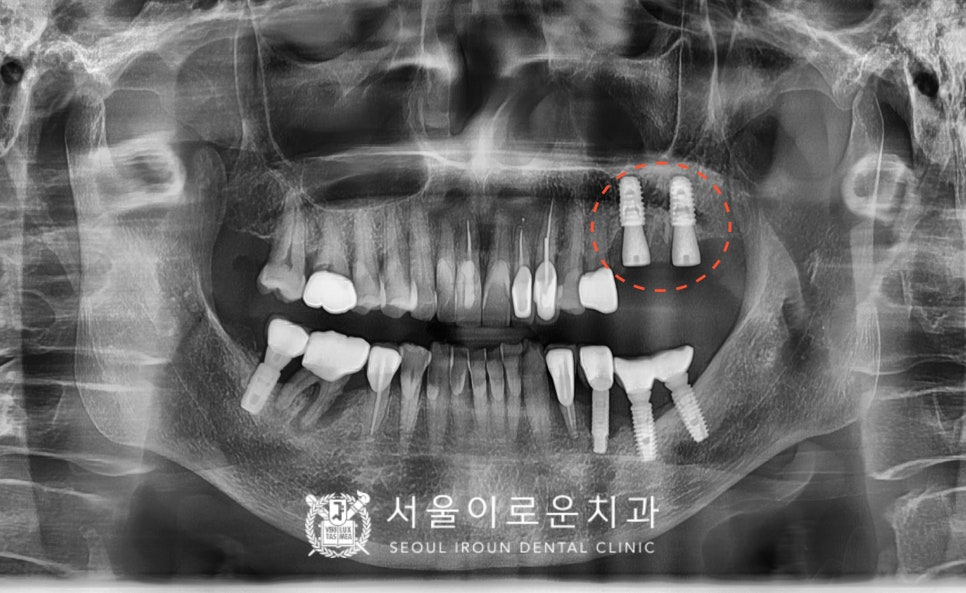

임플란트 식립 후

임플란트와 치조골이 단단하게 결합되기를

3~4개월 정도 충분히 기다린 후

osstell beacon이라는

골 유착을 확인할 수 있는 장비를 이용하여

isq(골유착정도) 측정하여

안정 값을 확인한 뒤

보철물 제작 인상채득을 진행했습니다.